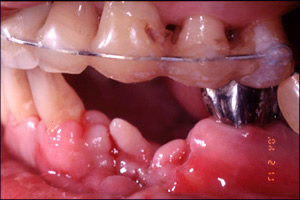

CASE4: 外傷による損傷の症例 主訴:打撲により、水平垂直に骨が欠損した状態をインプラントと骨移植により回復した。